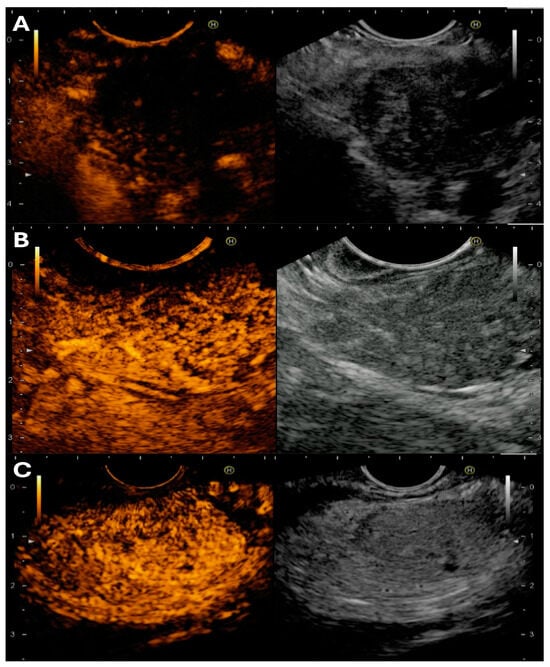

3.4. Advanced EUS Imaging to Guide Tissue Acquisition

3.4.1. Technique of Performing Advanced EUS Imaging

3.4.2. Basic Interpretation of Findings on CH-EUS and EUS-E

3.4.3. Data on Use of CH-EUS vs. Standard B-Mode for FNA/B for Pancreatic Tissue Sampling